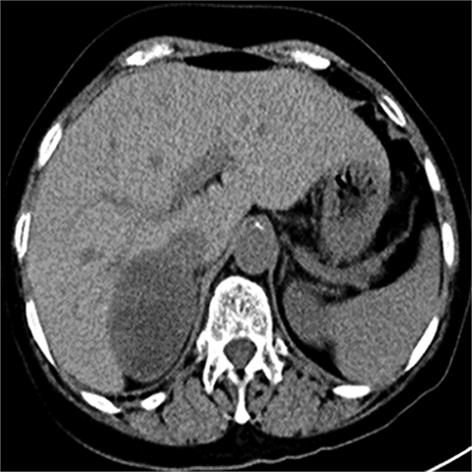

• 嗜铬细胞瘤及副神经节瘤不同生化表型的CT征象对比研究

2024, 49(2):203-209. DOI: 10.13406/j.cnki.cyxb.003433

摘要 (51) HTML (33) PDF 3.10 M (96) 评论 (0) 收藏

摘要:目的 分析生化阴性嗜铬细胞瘤及副神经节瘤(pheochromocytomas and paragangliomas,PPGLs)的电子计算机断层扫描(computed tomography,CT)征象是否有别于生化阳性PPGLs,同时了解生化阳性PPGLs不同表型的CT征象是否存在差异。方法 回顾性分析131例PPGLs患者的术前腹部增强CT图像,包括肿瘤位置、大小、形态、囊变坏死、液-液分层、钙化、向心结节状强化、肿瘤内粗大血管、强化包膜、绝对廓清率及相对廓清率。根据生化水平,将患者分为生化阳性组和阴性组,阳性组进一步分为去甲肾上腺素型、肾上腺素型及多巴胺型。比较各组及各表型间的CT征象差异。结果 相较于生化阴性组,阳性组PPGLs更大(Z=-2.064,P=0.039)、囊变坏死(χ2=6.610,P=0.010)及向心结节状强化(χ2=3.909,P=0.048)的比例更高;相较于去甲肾上腺素型,肾上腺素型PPGLs更大(Z=-2.036,P=0.042)、强化包膜比例更高(χ2=7.242,P=0.007)。结论 肿瘤大小、囊变坏死及向心结节状强化的CT征象有助于术前诊断生化阴性PPGLs,肿瘤大小及强化包膜有助于解释去甲肾上腺素型及肾上腺素型PPGLs不同临床表现产生的机制。